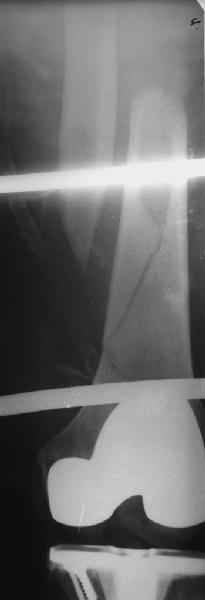

Уважаемые коллеги! 5.08.11 синтез бедренной кости пластиной LCP для дистального бедра.

Прошу совета. П-ка, 59 лет, автодорожная травма, перелом винтообразный н/3 левой бедренной кости. Планировалась закрытая репозиция и малоинвазивный доступ. по ходу операции пришлось немного открыть зону перелома для репозиции. Под контролем ЭОП вроде на столе смещение небольшое было и по оси терпимо. Сделали рентген контроль и получили вот картину. Еще обломилась головка кортикального винта. Синтез то стабильный. Только смещение не только не устранили, но кажется еще чуть больше стало (не могу) первичный снимок сделать). Склонен к ресинтезу и исправлению смещения из расширенного доступа. Как лучше выполнить репозицию? Какие можно использовать приемы репозиции? Спасибо.

конечно реостеосинтез, у Вас нижнии шуруп в линии перелома.

Коллега,для адекватной оценки перелома необходимо предоставлять предоперационные и послеоперационные снимки в двух проекциях. Насколько возможно судить по маленькой картинке прямой проекции, на первый взгляд тут простой винтообразный перелом 32-А1. В таком случае самый стабильный вариант накостного остеосинтеза - это стягивающий винт перепендикулярно линии перелома и нейтрализирующая пластина. Особых показаний к малоинвазивному мостовидному остеосинтезу нет, т.к. при нем ниже стабильность фиксации, и все микродвижения сконтрентрируются в сравнительно небольшой зоне перелома, что приведет к большим смещающим силам. Однако, если присмотрется, на снимке видно что линия перелома продолжается до начала медиального мыщелка, поэтому скорее всего это клиновидным перелом со спиральным клином 32-В1. В таких случаях возможно выполнение мостовидного синтеза, однако в данном случае дистальная часть клина не смещена относительно дистального конца бедренной кости, таким образом, мне кажется, биомеханически ситуация представляет собой среднее между А1 и чистым В1. Смещающие усилия концентрируются в проксимальной части перелома, тогда как в дистальной несмещенной части они минимальны, в т.ч. из-за интактной надкостницы. Поэтому в данном конкретном случае, при невозможности выполнения интрамедуллярного блокирующего остеосинтеза, я бы выполнил остеосинтез с двумя стягивающими винтами (с рассверливанием ближнего кортикала сверлом большего диаметра) и нейтрализирующего остеосинтеза пластиной. Причем пластина могла бы быть даже обычная.

На представленных снимках, репозиции нет, есть вальгус. Полагаю фиксация не стабильна. Перелом может и срастется, но это будет долго и без нагрузки. Если бы была использована обычная пластина, можно было бы попробовать малоинвазивно подтянуть дистальный отломок и зафиксиривовать парой винтов. Однако примененные блокирующие винты не позволят этого сделать. Как вариант, возможно открытся снизу удалить винты, сделать небольшой доступ в зоне перелома (или попробовать закрыто) ввести 1-2 винта для фиксации клина, и перепровести блокирующие дистальные винты. В любом случае, стабильность при любом из этих вариантов будет заведомо ниже чем при стягивающих винтах + нейтрализирующей пластине. Удачи.

Для принятия решения в данном случае желательно переделать прямую проекцию на длинной кассете с захватом коленного сустава - четче оценить оси, остаточные и качество фиксации; однако и имеющийся снимок не вызывает ощущения катастрофы - вполне неплохо должно срастаться.